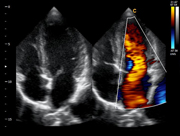

LV Longitude View, B Mode

Apical Four Chamber View, B Mode